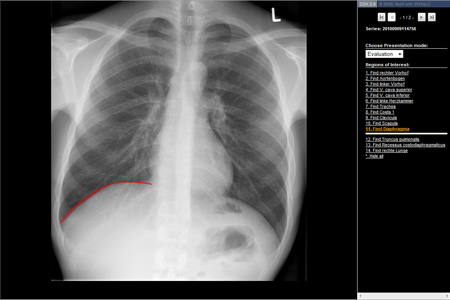

Mit dem Modus „Evaluation“ ist die Möglichkeit der Überprüfung des erlernten Wissens gegeben. Eine anatomische Struktur wird in der Liste ausgewählt und muss in dem gezeigten Bild mit der rechten Maustaste markiert werden. Ist die Auswahl richtig stellt sich die Struktur mit gesamtem Umfang dar (siehe Abb. 3).

Abb. 3 „Evaluate“ Röntgen-Thorax mit Abfrage einer einzelnen anatomischen Struktur